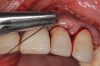

Following infiltration of the facial attached gingiva and palatal area with articaine hydrochloride 4% and epinephrine 1:100,000 (Septocaine®, Septodont [alternatively: Articadent®, Dentsply Sirona; Orabloc®, Pierrel]), an envelope releasing incision was made extending one full tooth over. To prevent trauma to the mucosal tissue, vertical incisions were not made (Figure 3). Incising the mucosa results in the release of prostaglandins and histamine, which increases postoperative discomfort. For this patient, staying in attached gingiva provided excellent control of the flap and allowed clear access to the apical lesion.

(3.) An envelope reflection was made with no vertical incisions, exposing the entire bony defect affecting the apical portion of the stable implant.

Figure 3